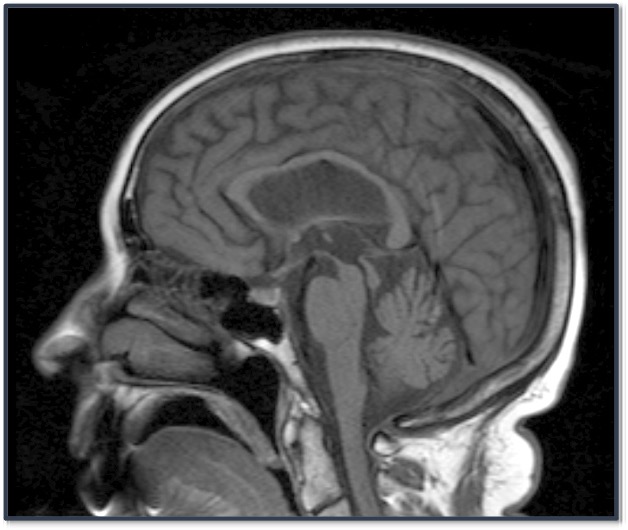

What is the classic imaging sign seen for PSP?

The Penguin Sign